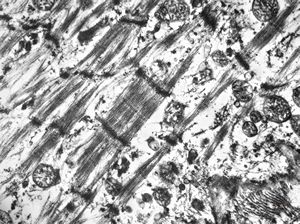

F,32y. | transversally sectioned skeletal muscle cell

mouse skeletal muscle cell - transversal section